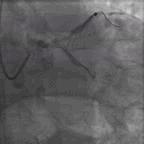

根据《中国经皮冠状动脉介入治疗指南(2016)》推荐,该患者适合CABG而非PCI。但是,患者及其家属拒绝行CABG,要求行PCI。在这种情况下,我们开始思索对该患者行PCI到底应处理哪支血管?左冠状动脉,还是右冠状动脉?经讨论后,首先对右冠状动脉进行干预(图3),治疗过程中AL.75指引导管导致右冠状动脉窦底夹层,此时很难抉择是放弃手术还是观察后干预前降支。观察10分钟后,见右冠状动脉窦底造影剂滞留逐渐消散。

图3. 对右冠状动脉行PCI